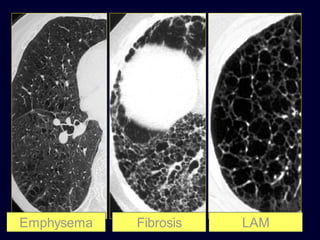

Emphysema

Fibrosis

LAM

Lymphangioleiomyomatosis

(LAM)

HRCT Morphology

Thin-walled cysts (2mm - 5cm)

Uniform in size / rarely confluent

Homogeneous distribution

Chylous pleural effusion

Lymphadenopathy

in young women

histopathological definition

…..permanent abnormal enlargement of

airspaces distal to the bronchioles terminales

and

…...destruction of the walls of the involved

airspaces